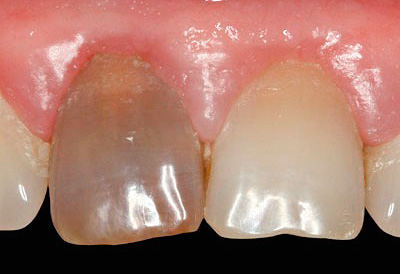

Foto de um dente com uma cárie profunda que atinge a câmara pulpar:

O processo purulento agudo, por sua vez, pode se espalhar sob o periósteo e causar um "fluxo", que muitas vezes leva à extração dentária. De um modo geral, a transição da fase fibrosa para a gangrena pulpar é desagradável em todos os sentidos: um odor podre da boca aparece, o dente fica cinza, reage fortemente ao calor e surgem riscos adicionais de complicações graves.

A pulpite gangrenosa (gangrena pulpar) pode ser confundida com fibrosa, mas sua diferença fundamental é a aparência do dente (tom acinzentado), odor putrefativo da cavidade, cárie na boca dos canais e dor ao sondar os canais. Além disso, o principal indicador no diagnóstico neste caso são os dados EDI, que atingem 60 μA com gangrena pulpar.